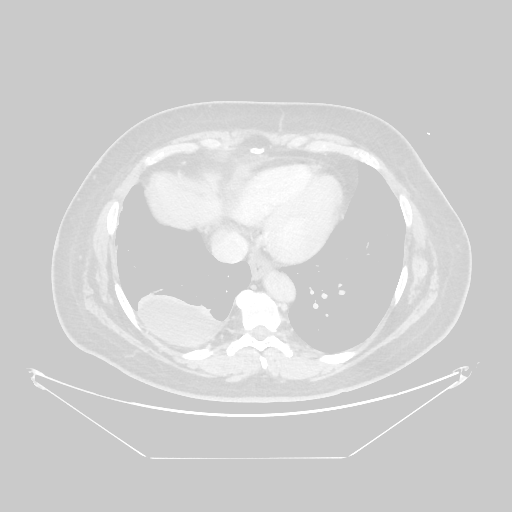

Image Grid

4×3 grid: Rows show different image types (Original NATIVE, Reconstructed NATIVE, Original VENOUS, Generated VENOUS), Columns show windowing techniques (No Window, Lung Window, Mediastinum Window)

Reconstructed NATIVE CT scan (cycle consistency)

No window - Raw intensity values

Reconstructed NATIVE CT scan (cycle consistency)

Lung window (WL -600, WW 1500 → Low −1350, High +150)

Reconstructed NATIVE CT scan (cycle consistency)

Mediastinum window (WL 40, WW 400 → Low −160, High +240)